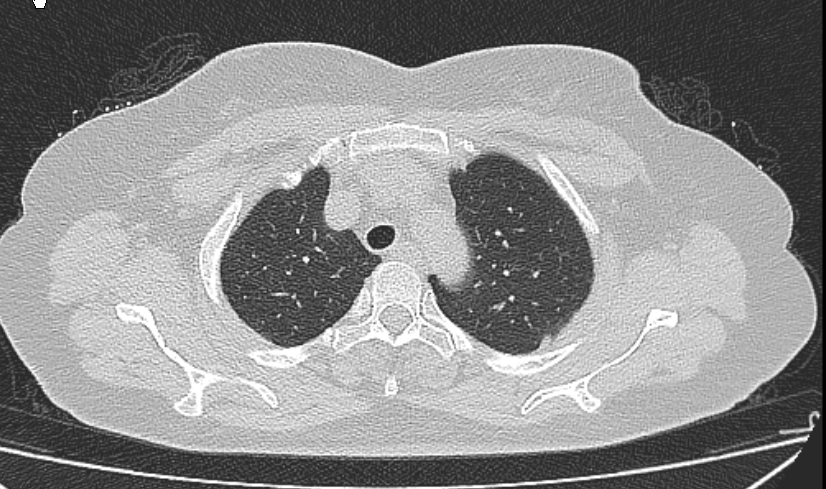

肺窗薄层1.5mm

V